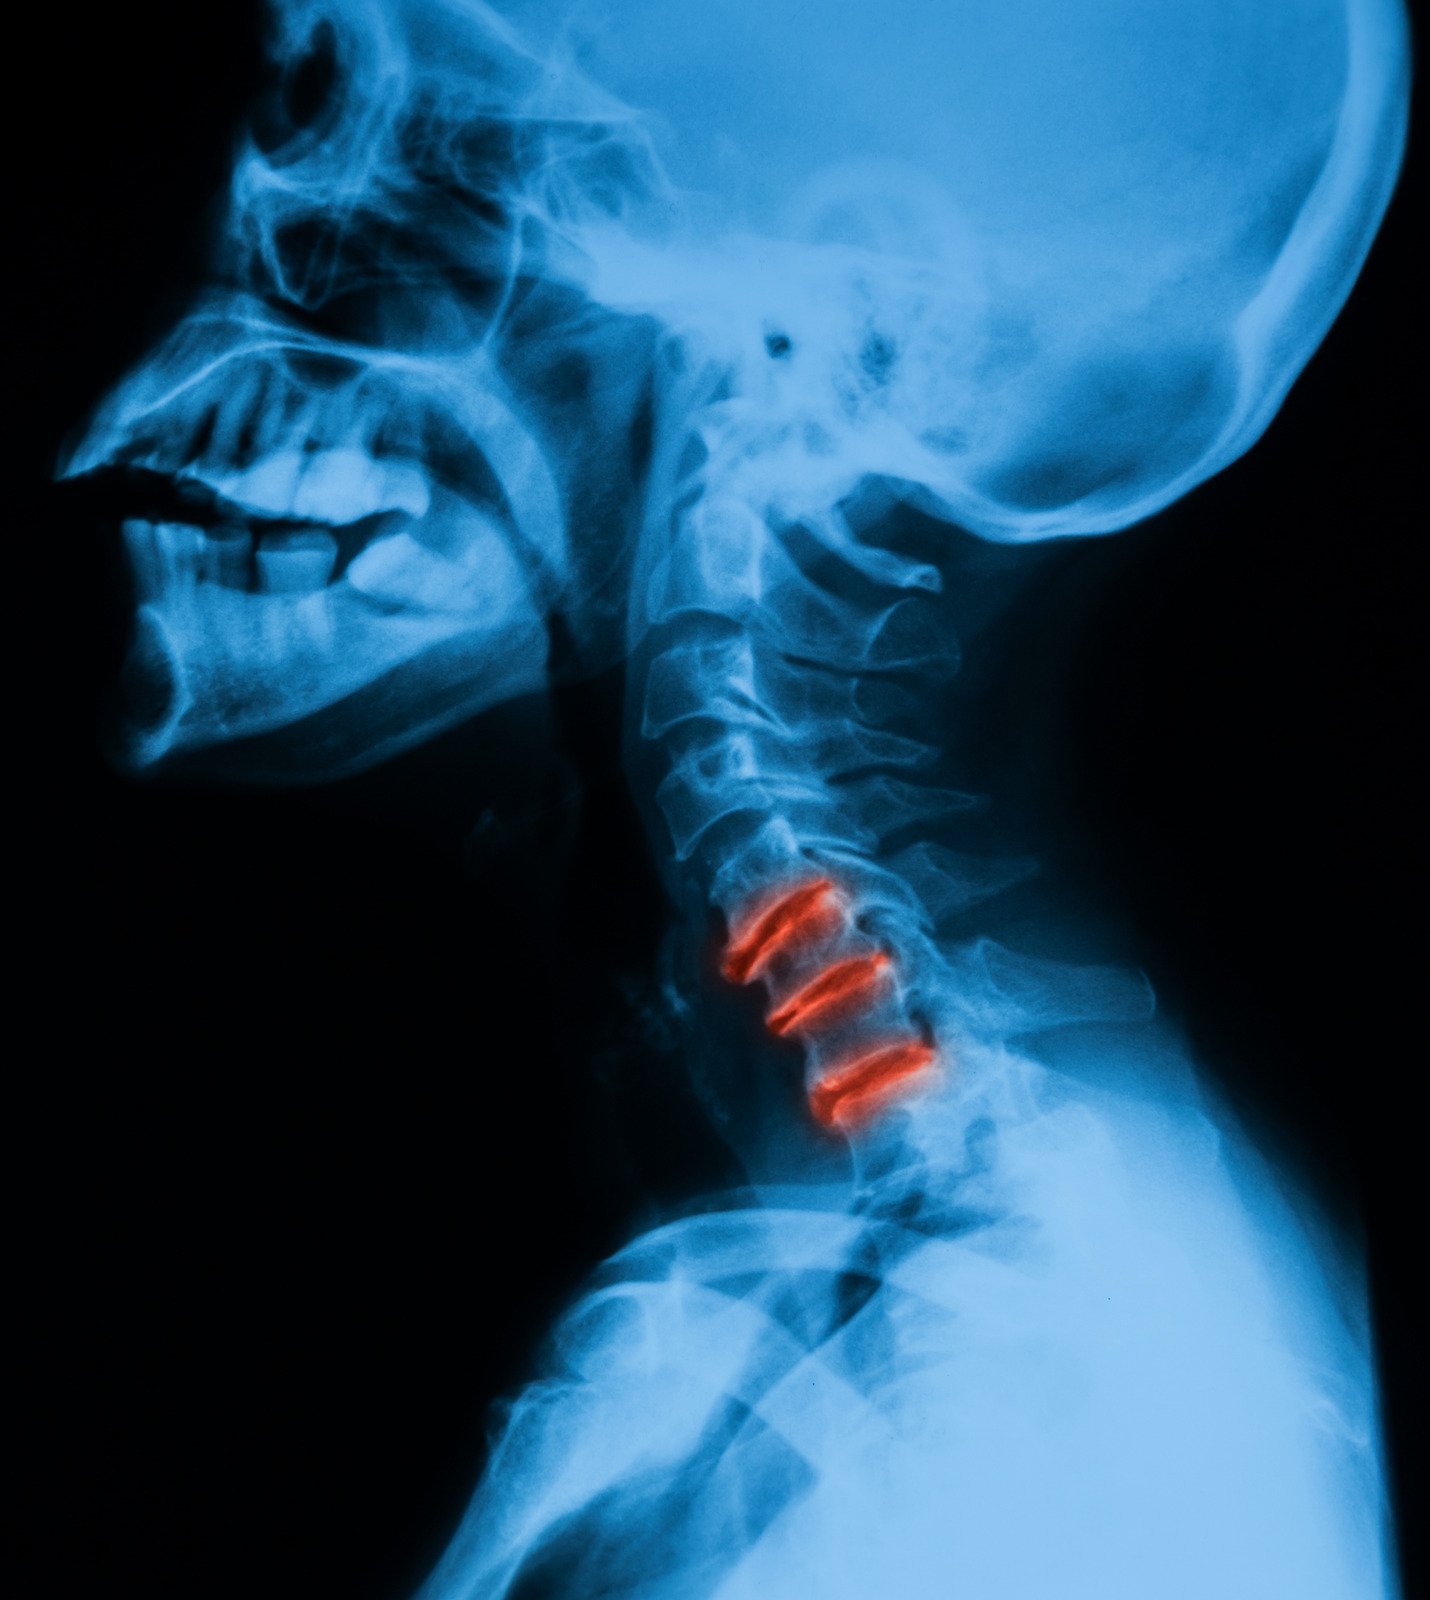

목 통증의 원인과 증상, 치료 방법

목 통증은 많은 사람들이 경험하는 일반적인 문제로, 다양한 원인에 의해 발생할 수 있습니다.

퇴행성 변화: 나이가 들면서 목 디스크나 척추에 퇴행성 변화가 생겨 통증을 유발할 수 있습니다.